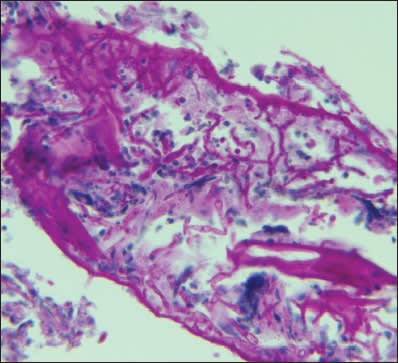

Intraocular cultures, which had previously been negative at the first vitrectomy, were positive for Aspergillus fumigatus, both from the capsular bag and from the vitrectomy specimens (Figure 3). The patient then received intravitreal amphotericin B (5μg/0.1 mL), a two-week course of oral voriconazole (200 mg bid), and was maintained on oral fluconazole (100 mg daily) for three months. Inflammation of the left eye gradually improved with this treatment. Ten months later, an anterior-chamber IOL was implanted and BCVA improved to 20/20 in the left eye (Figure 4). The fellow eye was unremarkable with 20/20 visual acuity.

Figure 3. Special stains of the capsular bag show numerous septated fungal hyphae consistent with Aspergillus fumigatus. Cultures confirmed this organism.